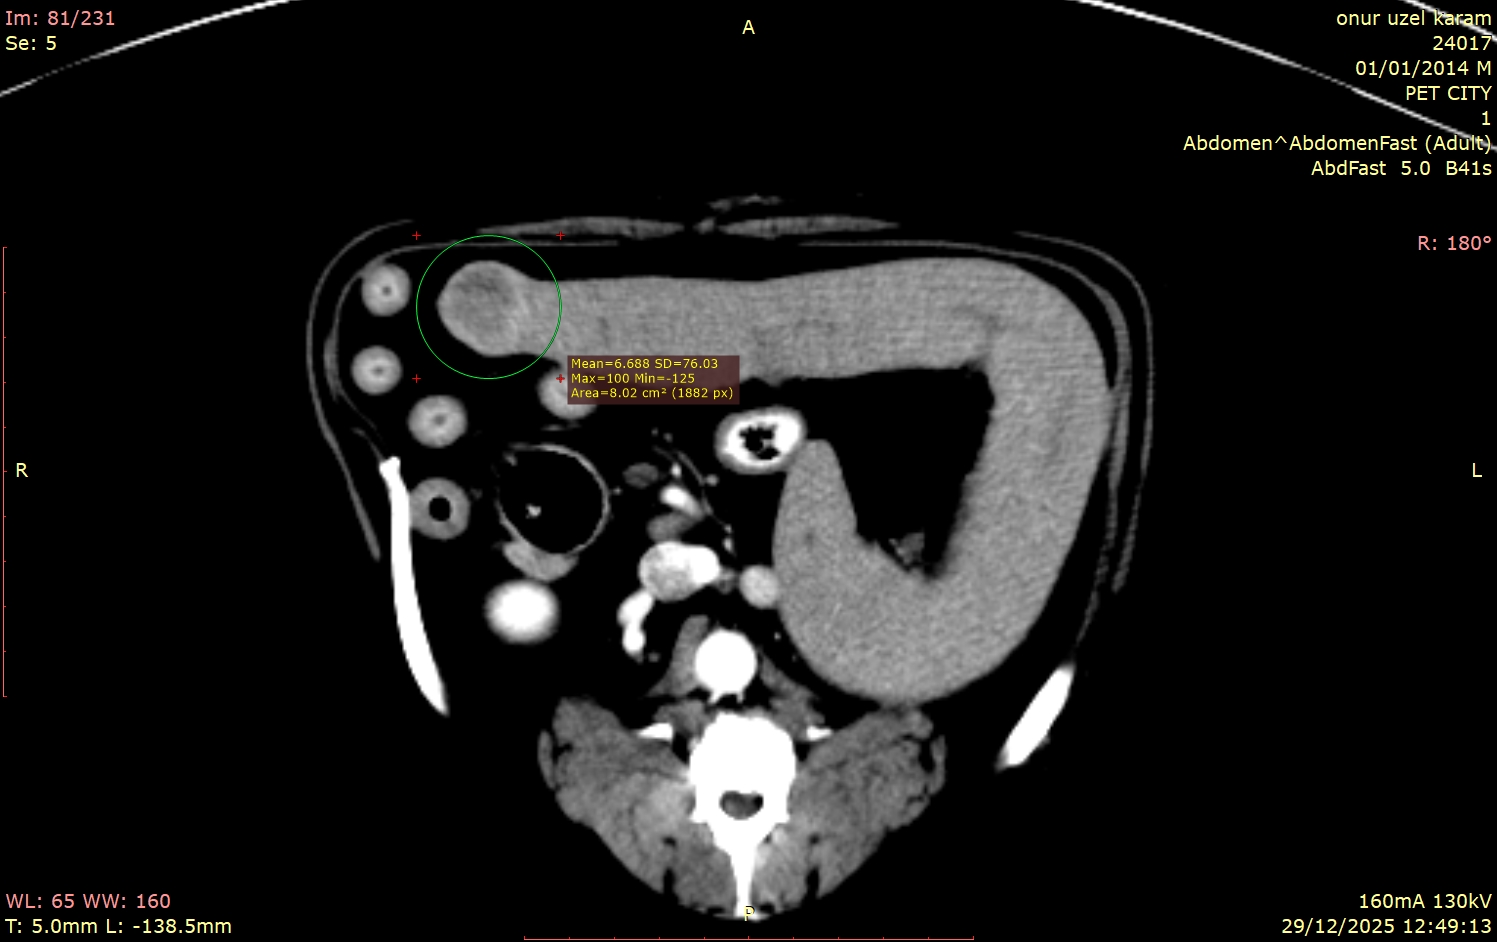

Hastamızın tomografi görüntülerini incelediğimizde, bizi şaşırtan ve tedavi planımızı kökten etkileyen detaylarla karşılaştık:

Bu vakadaki en kritik nokta, dalaktaki kitlenin tamamen "sessiz" olmasıydı. Hasta sahibinin fark edebileceği hiçbir semptom yoktu. Eğer sadece prostata odaklanıp ileri görüntüleme tekniklerini kullanmasaydık, dalaktaki bu lezyon gözden kaçabilirdi.

Tomografi çekilmemiş olsaydı, bu kitle belki de çok daha ileri bir evrede, tedavi şansının azaldığı bir dönemde karşımıza çıkacaktı. Bu vaka, tomografinin yalnızca mevcut problemi çözmekle kalmayıp, henüz belirti vermeyen gizli tehlikeleri de erken dönemde yakalama gücünü net bir şekilde göstermektedir.